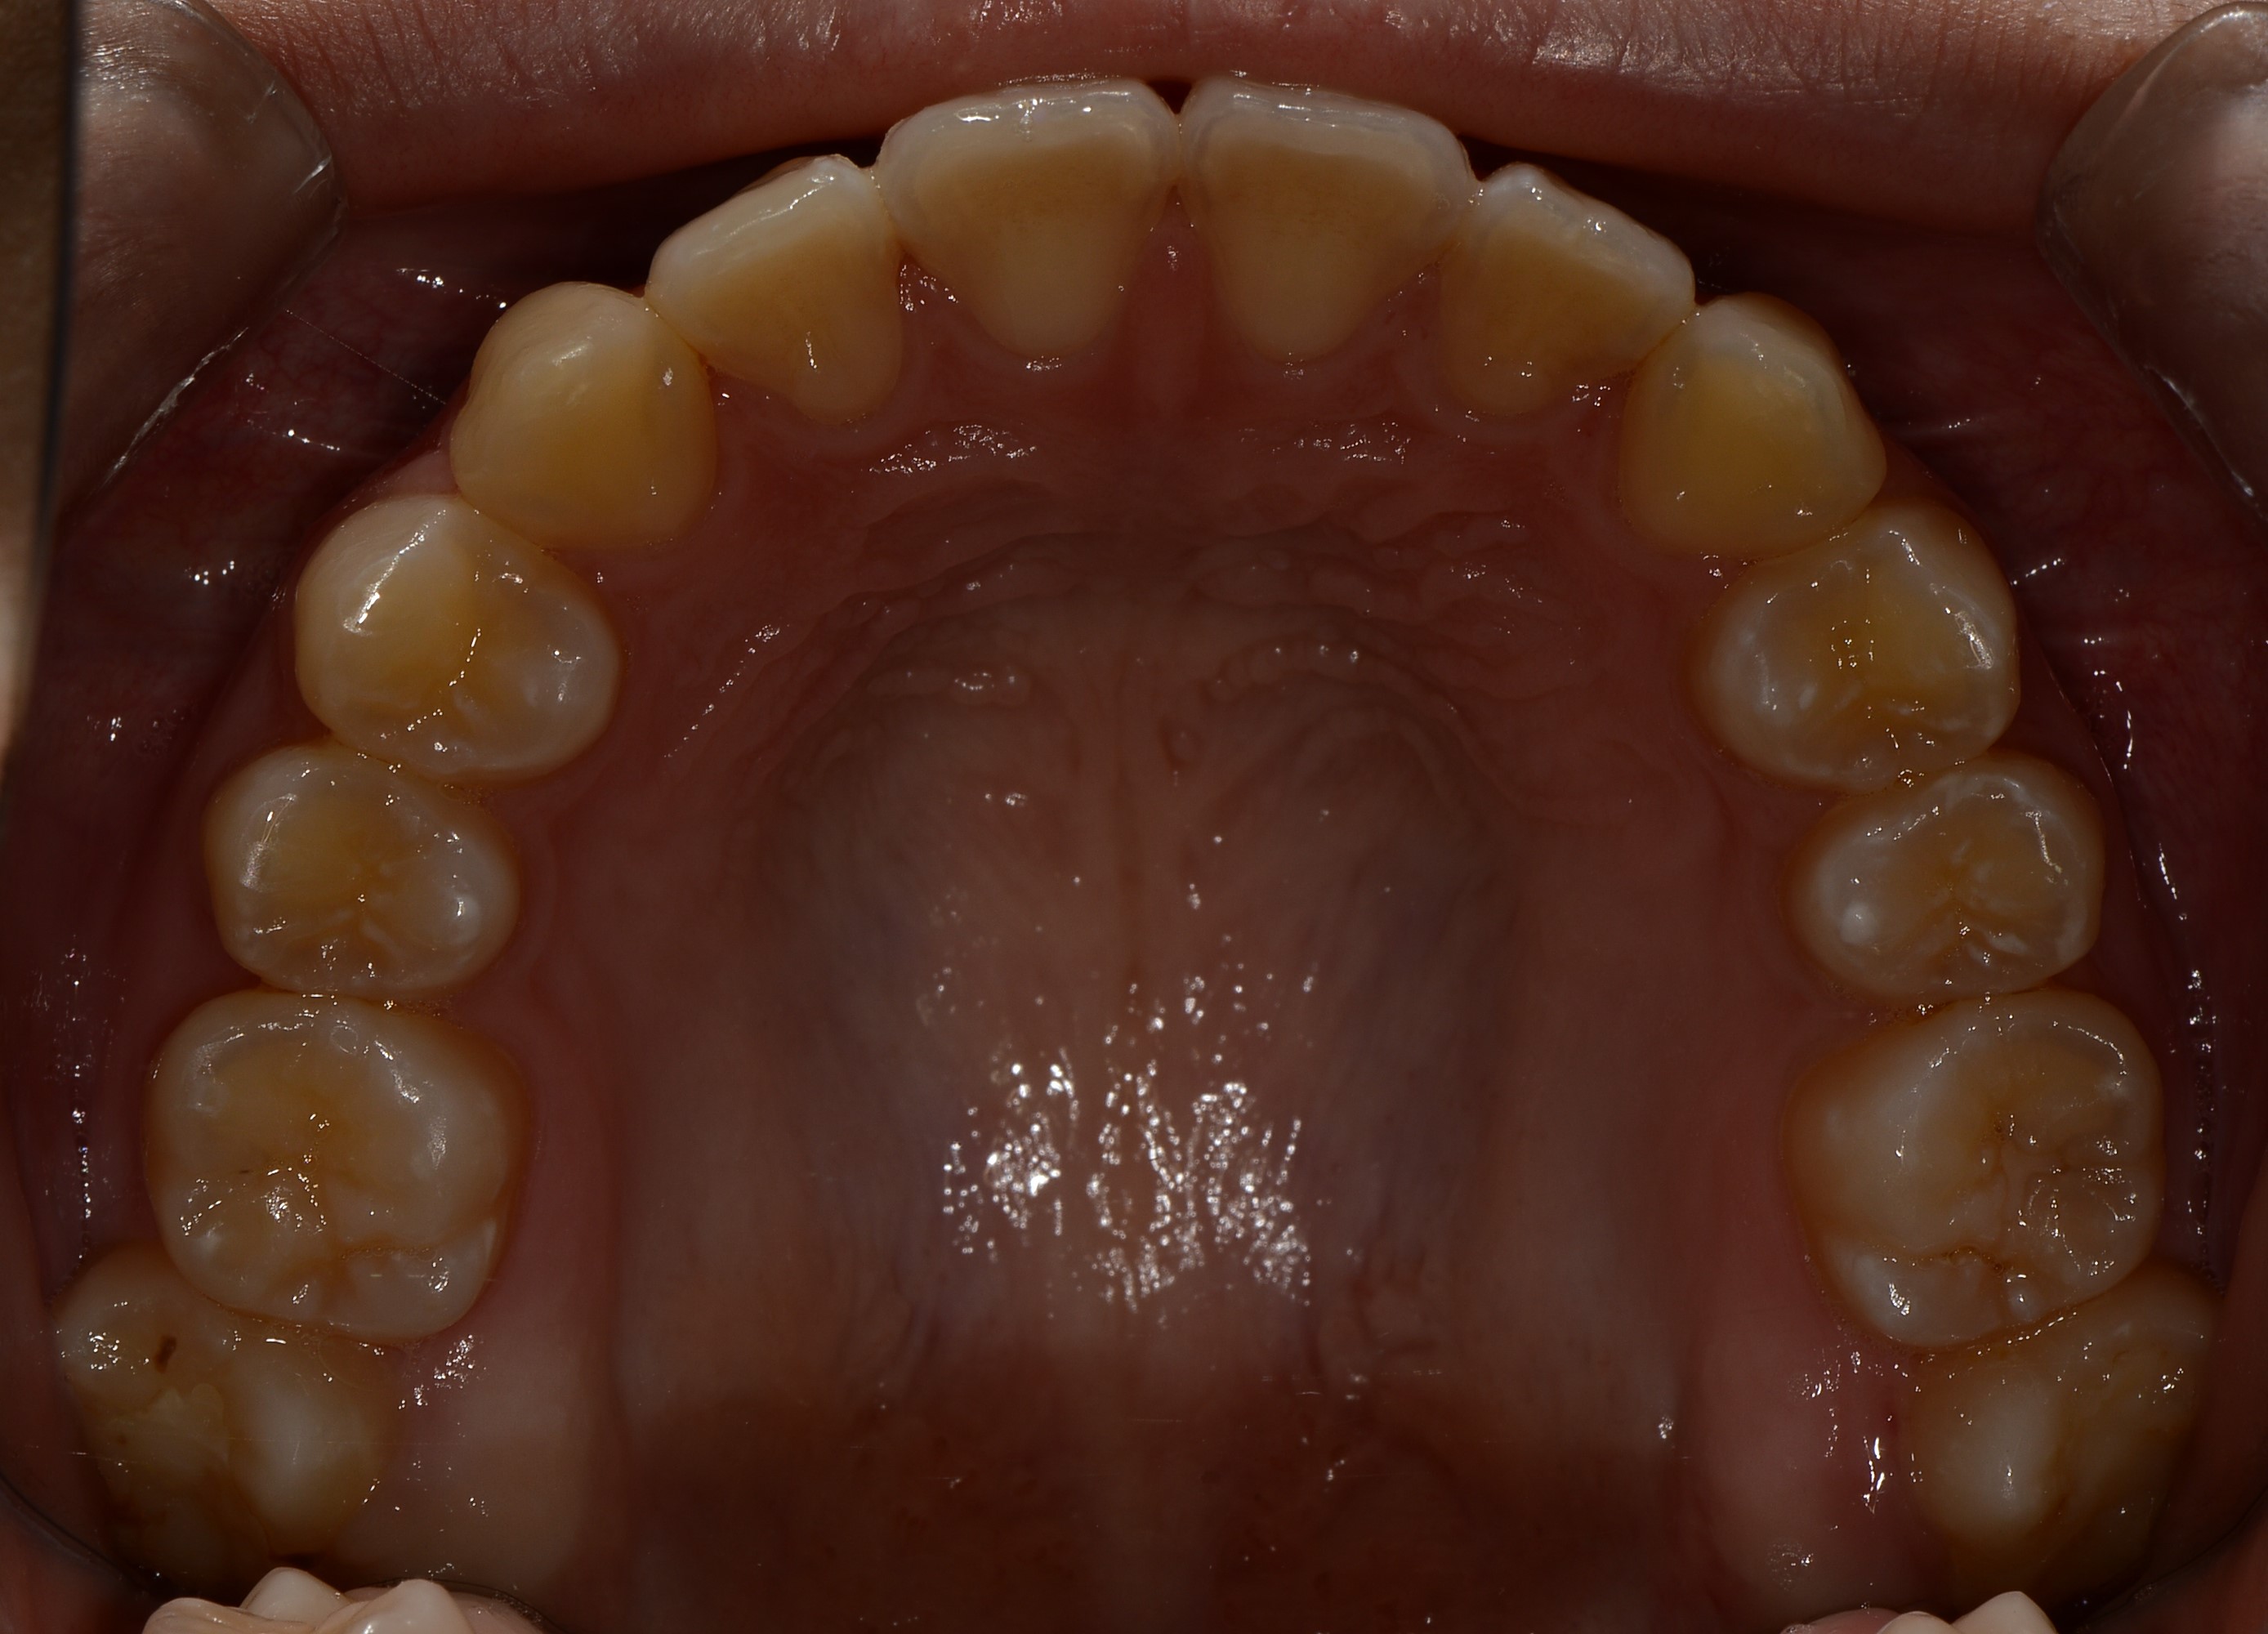

치료 전 사진입니다.